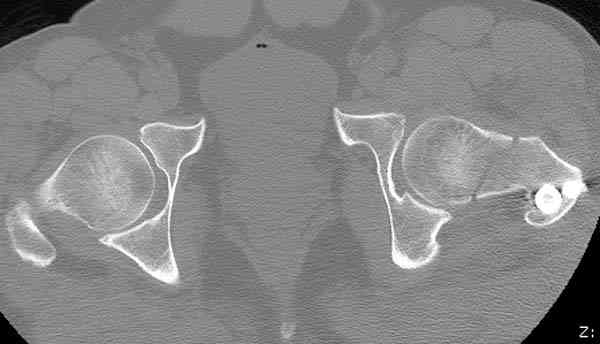

Здесь представлены снимки больного 65 лет, поступившего с диагнозом перелом

бедра после автоаварии.

На второй день (7) обнаружен пропущенный перелом,

сделаны Компьютерная Томограмма